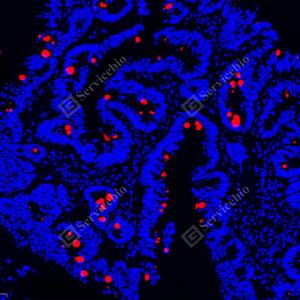

IF检测MUC2蛋白(货号 GB15344)(红色). 样品: 人小肠, 4%多聚甲醛 (货号G1101) 固定12-24小时. 抗原修复: 柠檬酸抗原修复液(干粉, pH 6.0) (G1201), 高压锅均匀喷气计时2分钟. 封闭: 3% BSA(货号GC305010)的PBS溶液, 室温孵育30分钟. —抗: 1: 1000稀释, 4℃ 孵育过夜. 二抗: Cy3标记山羊抗兔IgG (H+L) (货号GB21303), 1: 300稀释, 室温孵育1小时. |